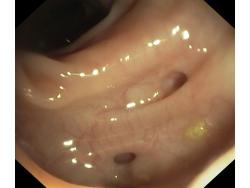

Uchyłki